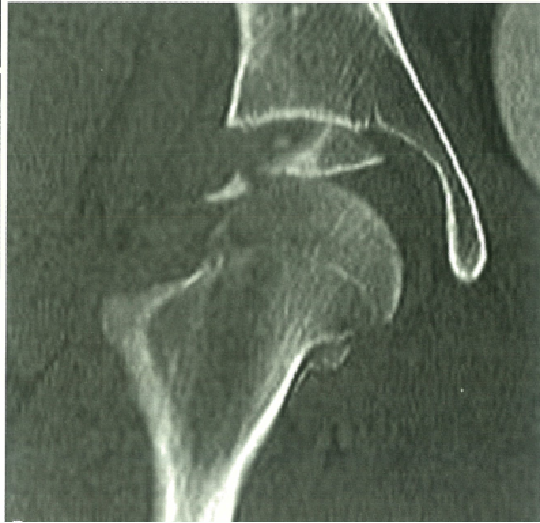

CT :  关节内残留的骨软骨碎块?有无髋臼骨折?